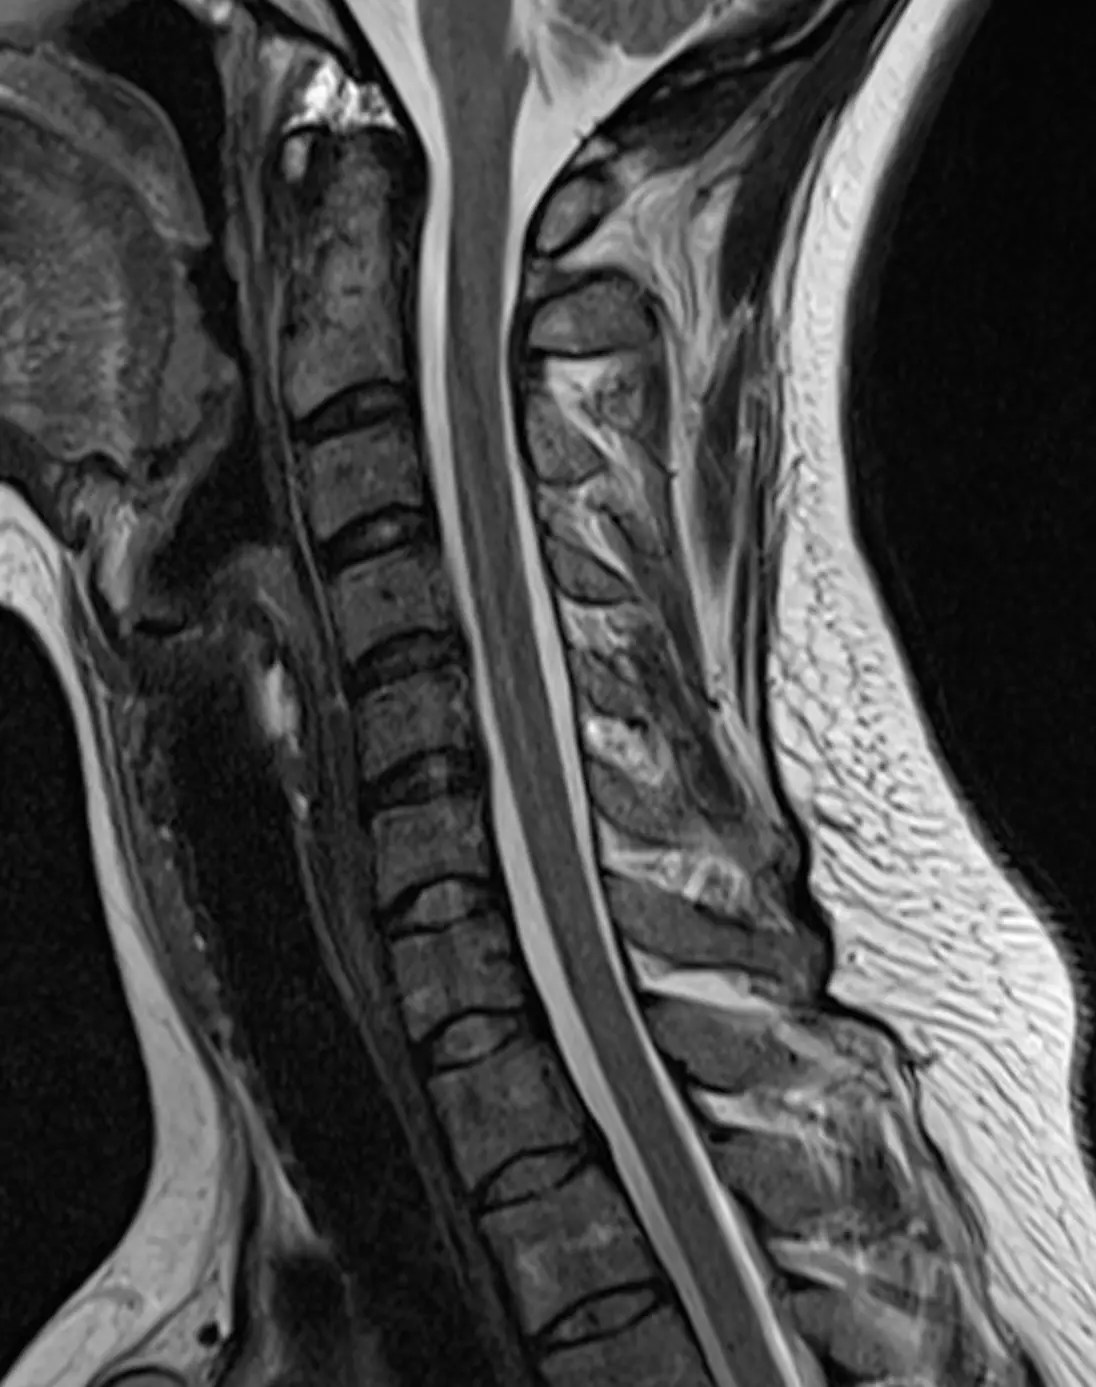

Визуализация слюнных желез, лимфатических узлов, щитовидной железы, воздушный просвет носоглотки, гортани, видимых отделов трахеи.

Показания:

— Дополнительные объемные образования, воспалительные процессы

— Лимфаденопатия

— Изменения в структуре щитовидной железы и т.д.